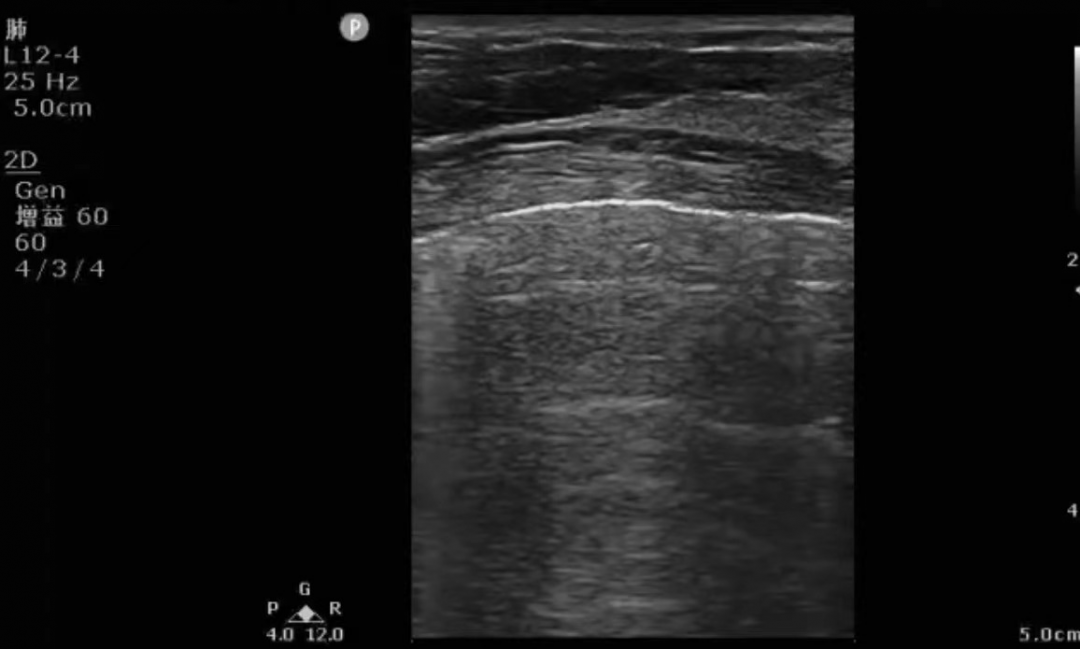

床旁超声是重症医生在接触重症病人时首先使用到的关键设备,因其具有多部位实时动态监测、无创安全、方便快捷的特点,备受重症医生青睐。在急危重患者的治疗和护理工作中发挥着不可忽视的作用,在循环治疗、呼吸治疗、营养支持、容量评估、血管评估、压力性损伤的评估与干预、判断胃残余量及评估膀胱容量等方面得到了广泛的应用,同时在院感防控中也起到了非常重要的作用。

用它我们可以即时评估患者心、肺、肾、胃肠道、颅内等重要脏器功能和血流动力学状态,排除某些危险性疾病(如急性心包填塞、急性心内梗阻、急性肺栓塞、气胸、急性腹腔出血等),进行各种高难度的血管和体腔的穿刺等。在病人病情逐步稳定后,我们可以再次通过超声评估病人治疗后的反应、发现某些潜在的高危因素(如深静脉血栓、肺水肿形成等)。